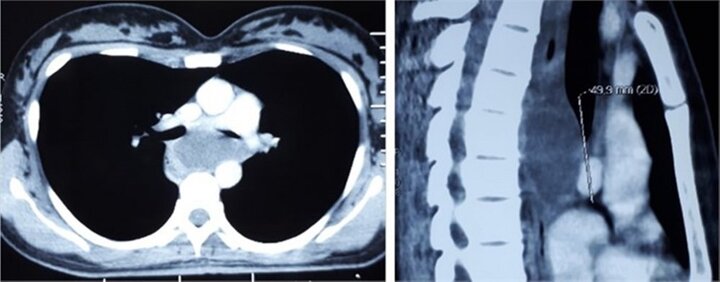

Kỳ lạ: Người phụ nữ ‘có kén’ trong phế quản

Bệnh viện Trung ương Quân đội 108 vừa cấp cứu thành công một bệnh nhân bị kén phế quản khá hiếm.